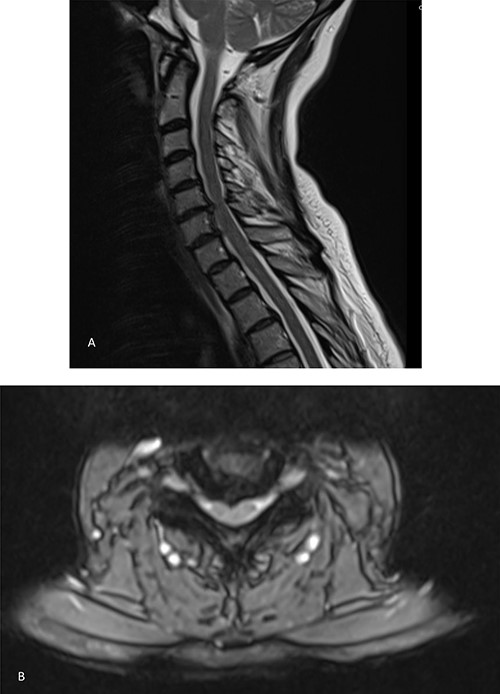

She was further referred for spinal magnetic resonance imaging (MRI) which revealed a C5–C6 disc compression (Fig. 1). Following the scan, she was further referred to neurosurgery where a discussion was carried out with regards to the risks and benefits of surgery to relieve the pressure on the nerves. Given the thecal compression and the significant pruritus refractory to any therapy, the decision was to proceed with a surgical intervention.

MRI showing bilateral C6 nerve root compression and left C7 nerve compression, C5–C8 disc herniation indenting the ventral aspect of the cord without typical signs of compression myelopathy or significant intramedullary signal abnormality. A. Sagittal view. B. Axial view.